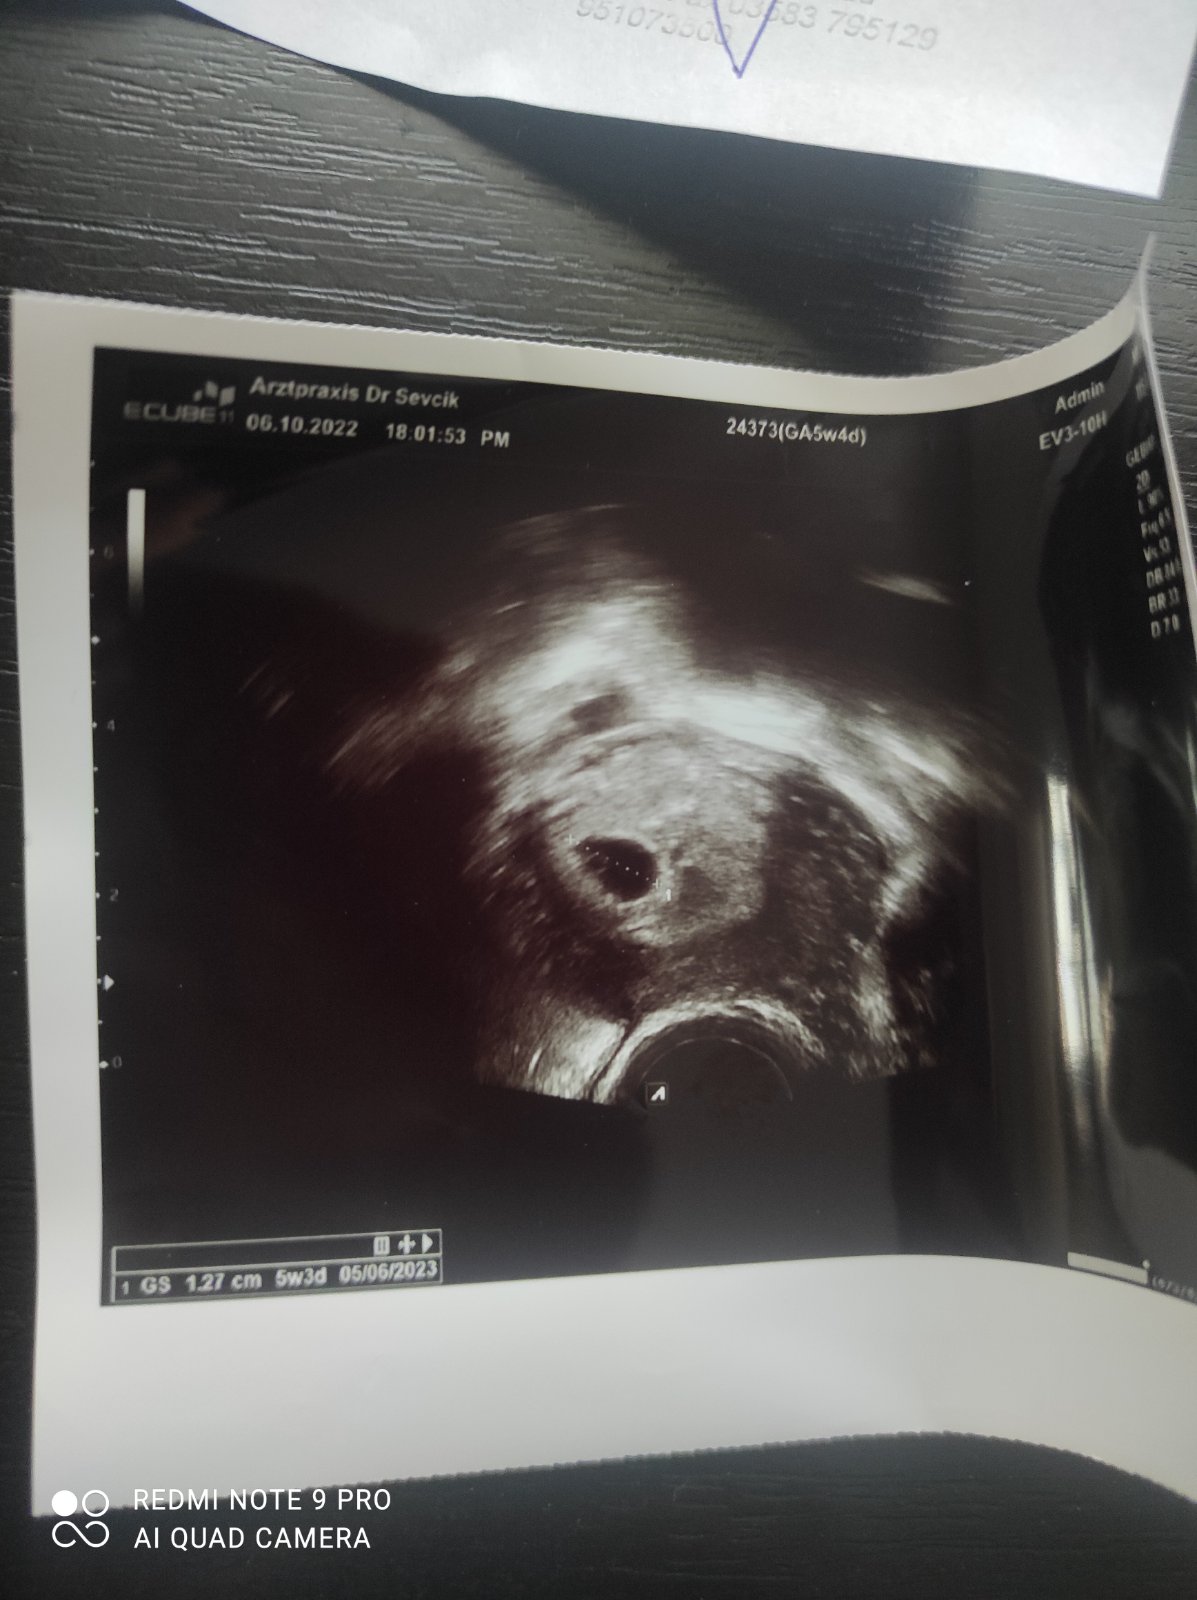

ahoj jsem v 5+3 a nejsem si moc jistá zda něco vidím a jak sem byla z toho tak nějak zaskočená na gynekologii tak sem se ani nezeptala co tam přesně vidí pan Doktor a aby mi to popsal , myslíte že je to takhle v pořádku?

Dutinka, v tomto týdnu normální. Zjistí se tak jedině, zda to není mimoděložní (to asi není, jinak by ti to řekl).